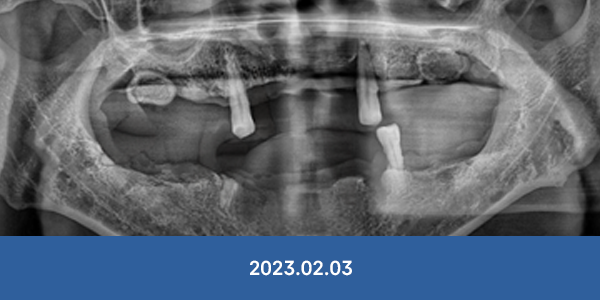

풍부한 임상 경험을 가진 대표원장이 처음 상담부터

수술, 사후관리까지 전 과정 직접 책임집니다.

정확한 진단과 안전한 수술로 오래 쓰는 임플란트를 약속드립니다.

임플란트 식립 개수

연간 3천개

최근 6년 임플란트 식립개수 누적 1만3천개 돌파

임플란트 수술, 경험이 곧 실력입니다.